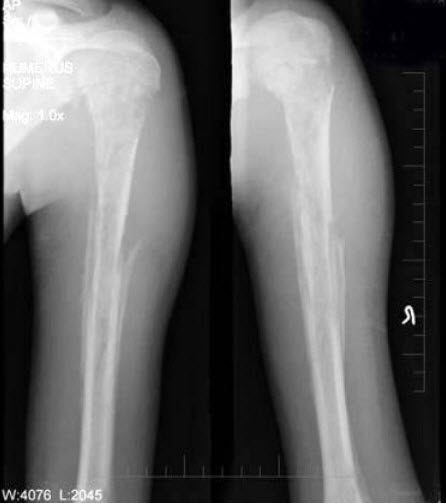

115、单项选择题

男,15岁,畏寒,高热2周,摄片如图所示,下列描述正确的是()

A.骨质广泛性溶骨性破坏

B.少许骨质增生硬化

C.大量层状骨膜增生

D.以上描述均正确

E.以上描述均不正确